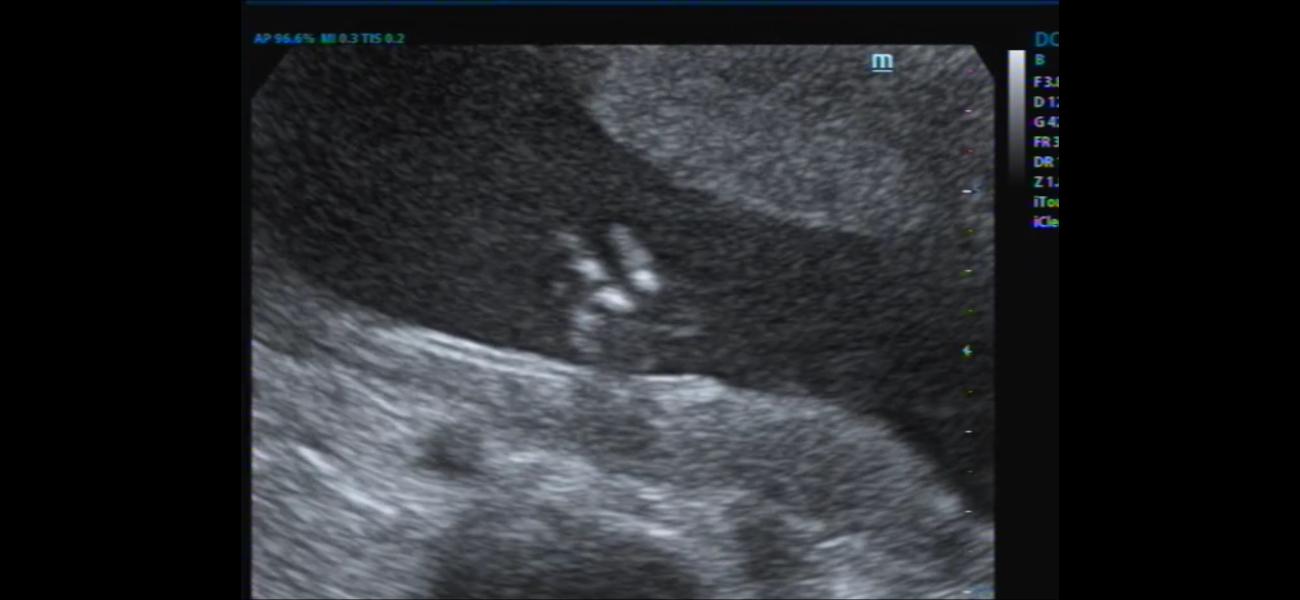

Сходила позавчера с мужем на 2 скрининг,сказали что с развитием все хорошо-но врач не смогла найти 3 фаланг мизинчика на кисти,и показала что на ножках большой пальцы оттопыренны (4 фото видео с узи-муж говорит все видно,а на ногах у тебя также оттопырен палец ),при 1 скрининге сдала кровь,низкие риски на 21 хромосому.